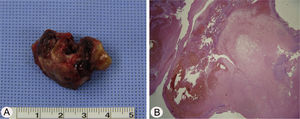

Case reportA 17-year-old male was referred to our outpatient clinic because of recurrent epistaxis after left nasal polypectomy. He had undergone nasal polypectomy due to nasal congestion at a local clinic 10 days ago. He had neither other symptoms nor any medical history. There was no history of trauma and no sign of allergy. The endoscopic examination revealed bulging of lateral nasal wall and bleeding due to left maxillary sinus mass (Fig. 1A). A Computed Tomography (CT) scan of the paranasal sinuses showed heterogenous enhancing mass in left maxillary sinus without adjacent bony involvement (Fig. 1B and C). On Magnetic Resonance Imaging (MRI), the mass expanding left maxillary sinus had mixed high signal intensity on T1-weighted images (T1WIs) and heterogenous high signal intensity on T2-weighted images (T2WIs) with an avid enhancement (Fig. 1D–F). Considering the location of tumor, surgical access was gained via Caldwell-Luc approach under general anesthesia because transnasal endoscopic sinus surgery had high risk of bleeding. The mass was originated from medial wall and partial superior wall of left maxillary sinus (Fig. 2A and B). The base of the lesion including the healthy mucosa around it was successfully removed with harmonic scalpel and microdebrider under direct visualization using a nasal endoscope and cauterized using suction cautery for prevention of recurrence (Fig. 3A). Histopathologic examination showed variable sized and irregular shaped vascular spaces with thrombus, consistent with arteriovenous malformation (Fig. 3B). Postoperative course was uneventful and he was discharged five days after surgery. Endoscopic examinations and CT performed 3 months postoperatively showed no evidence of recurrence.

The most common presenting complaint of arteriovenous malformations of the maxillofacial region is chronic intermittent bleeding although some of these tumors have no signs or symptoms.1 Patients may present with headaches, buzzing, pain, pressure, toothache, earache, pulsation, epistaxis, swelling, facial asymmetry, ocular pain, teeth mobility, and compressibility of teeth into their sockets.1,3 Our patient's primary symptoms was recurrent nasal bleeding after nasal polypectomy with no other symptoms. Since our patient had no history of surgery or blunt trauma, we assumed that his arteriovenous malformation was congenital. It is important to differentiate arteriovenous malformation from hemangiomas. Histologically, arteriovenous malformation is made up of aberrant arteriovenous channels in communication with each other. The abundance of arterial (thick-walled) components with different sized shapes and adjacent thin-walled venous channel can help us to diagnose it as arteriovenous malformation.4